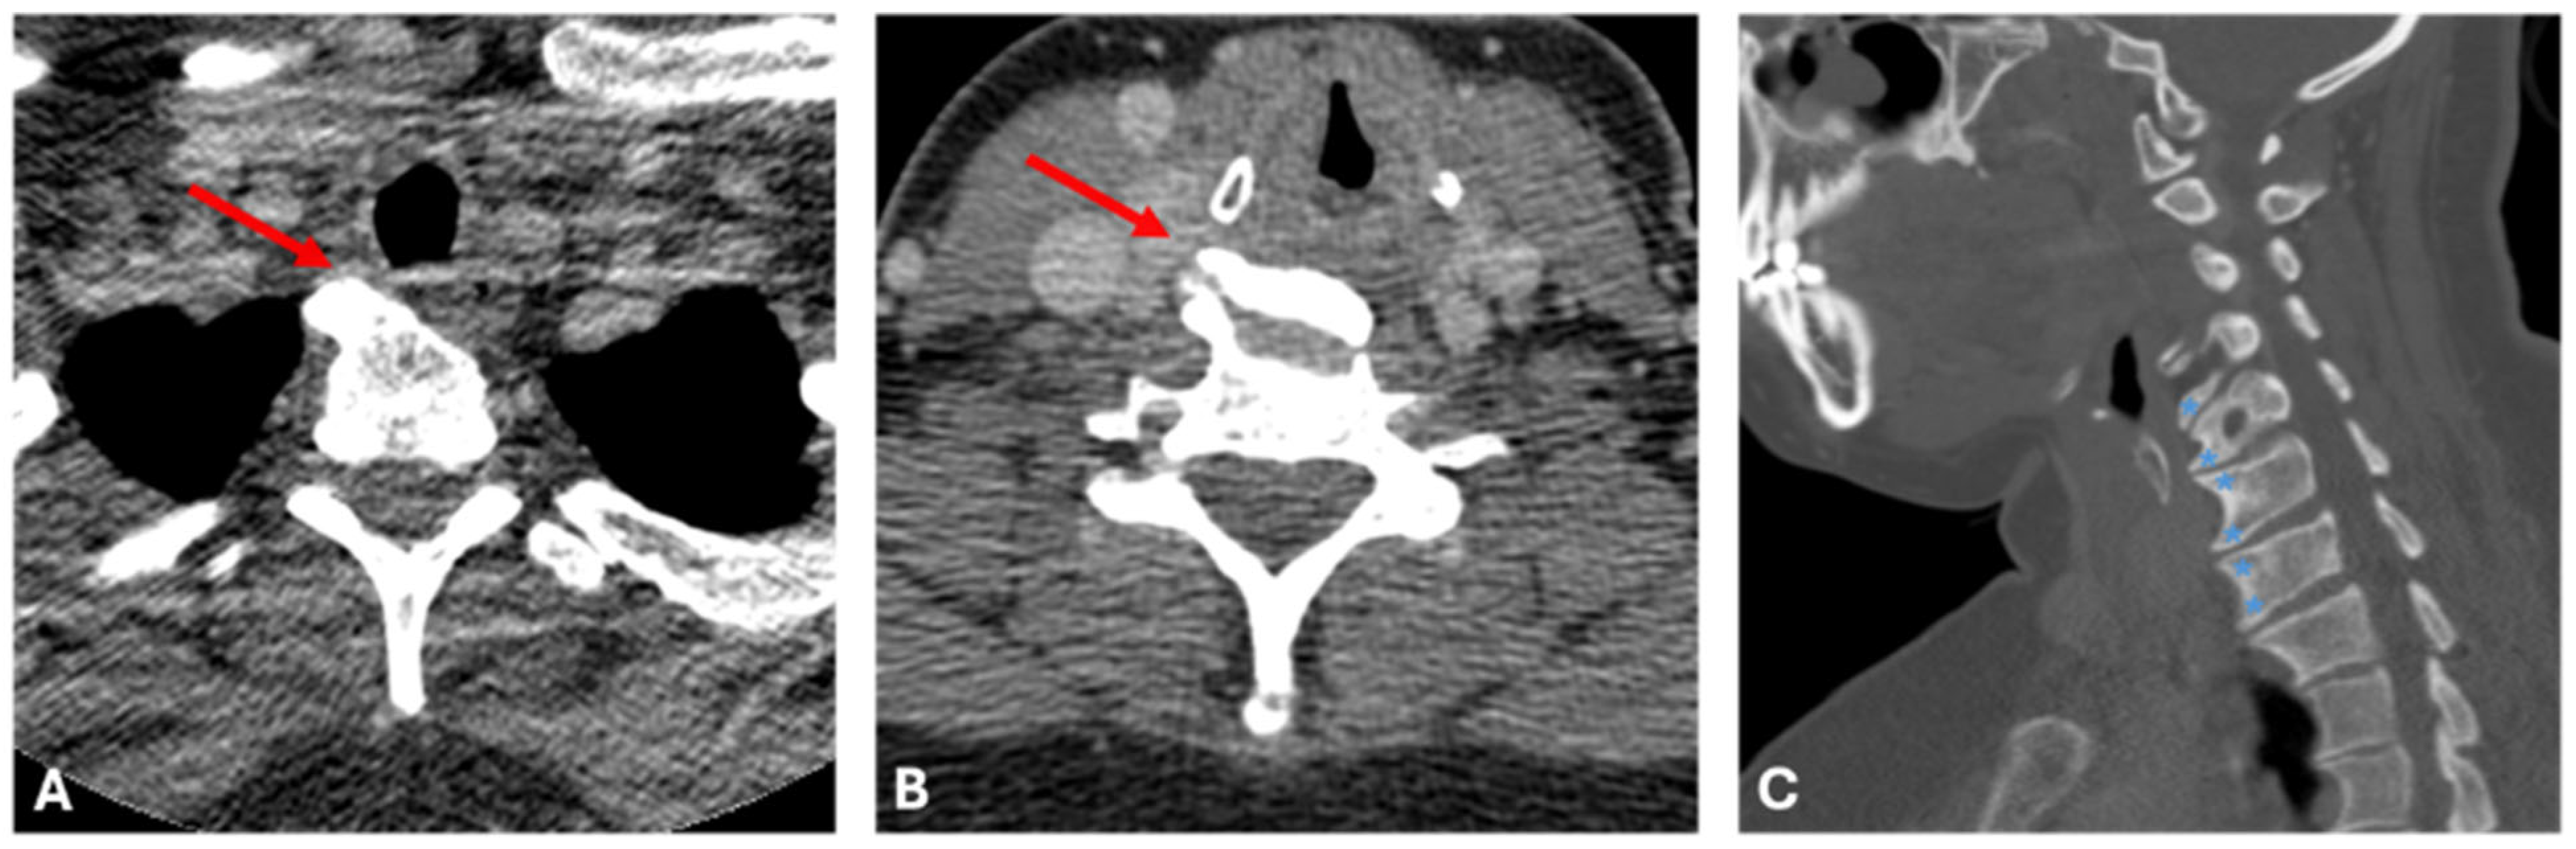

Figure 4.

Computed Tomography images for Case B. Axial soft tissue window CT images (A,B) demonstrate multi-level right-sided endplate osteophytes (red arrow) which project into the right tracheo-esophageal groove, along the expected course of the right recurrent laryngeal nerve, in this patient with right vocal cord paresis. Sagittal image (C) demonstrates multi-level bulky endplate osteophyte formation (blue asterisk), in the absence of significant disc degeneration, in keeping with DISH.

At this presentation, her VHI score was 17/40. Strobovideolaryngoscopy revealed mild (10–20%) subglottic stenosis with anterior and posterior shelf formation (Figure 3). A right cervical osteophyte was visualized, and moderate to severe right vocal fold paresis was noted, though glottic closure remained complete. CT of the neck demonstrated multiple right-sided osteophytes projecting into the right tracheoesophageal groove, along the course of the right recurrent laryngeal nerve, in the absence of significant disc degeneration (Figure 4A–C). These findings were consistent with DISH. The patient was referred to speech therapy for voice rehabilitation and counselled regarding potential injection laryngoplasty should symptoms persist or worsen. Subglottic stenosis remained unchanged on follow-up evaluation. The patient did not elect for further management of her osteophytes at this time.